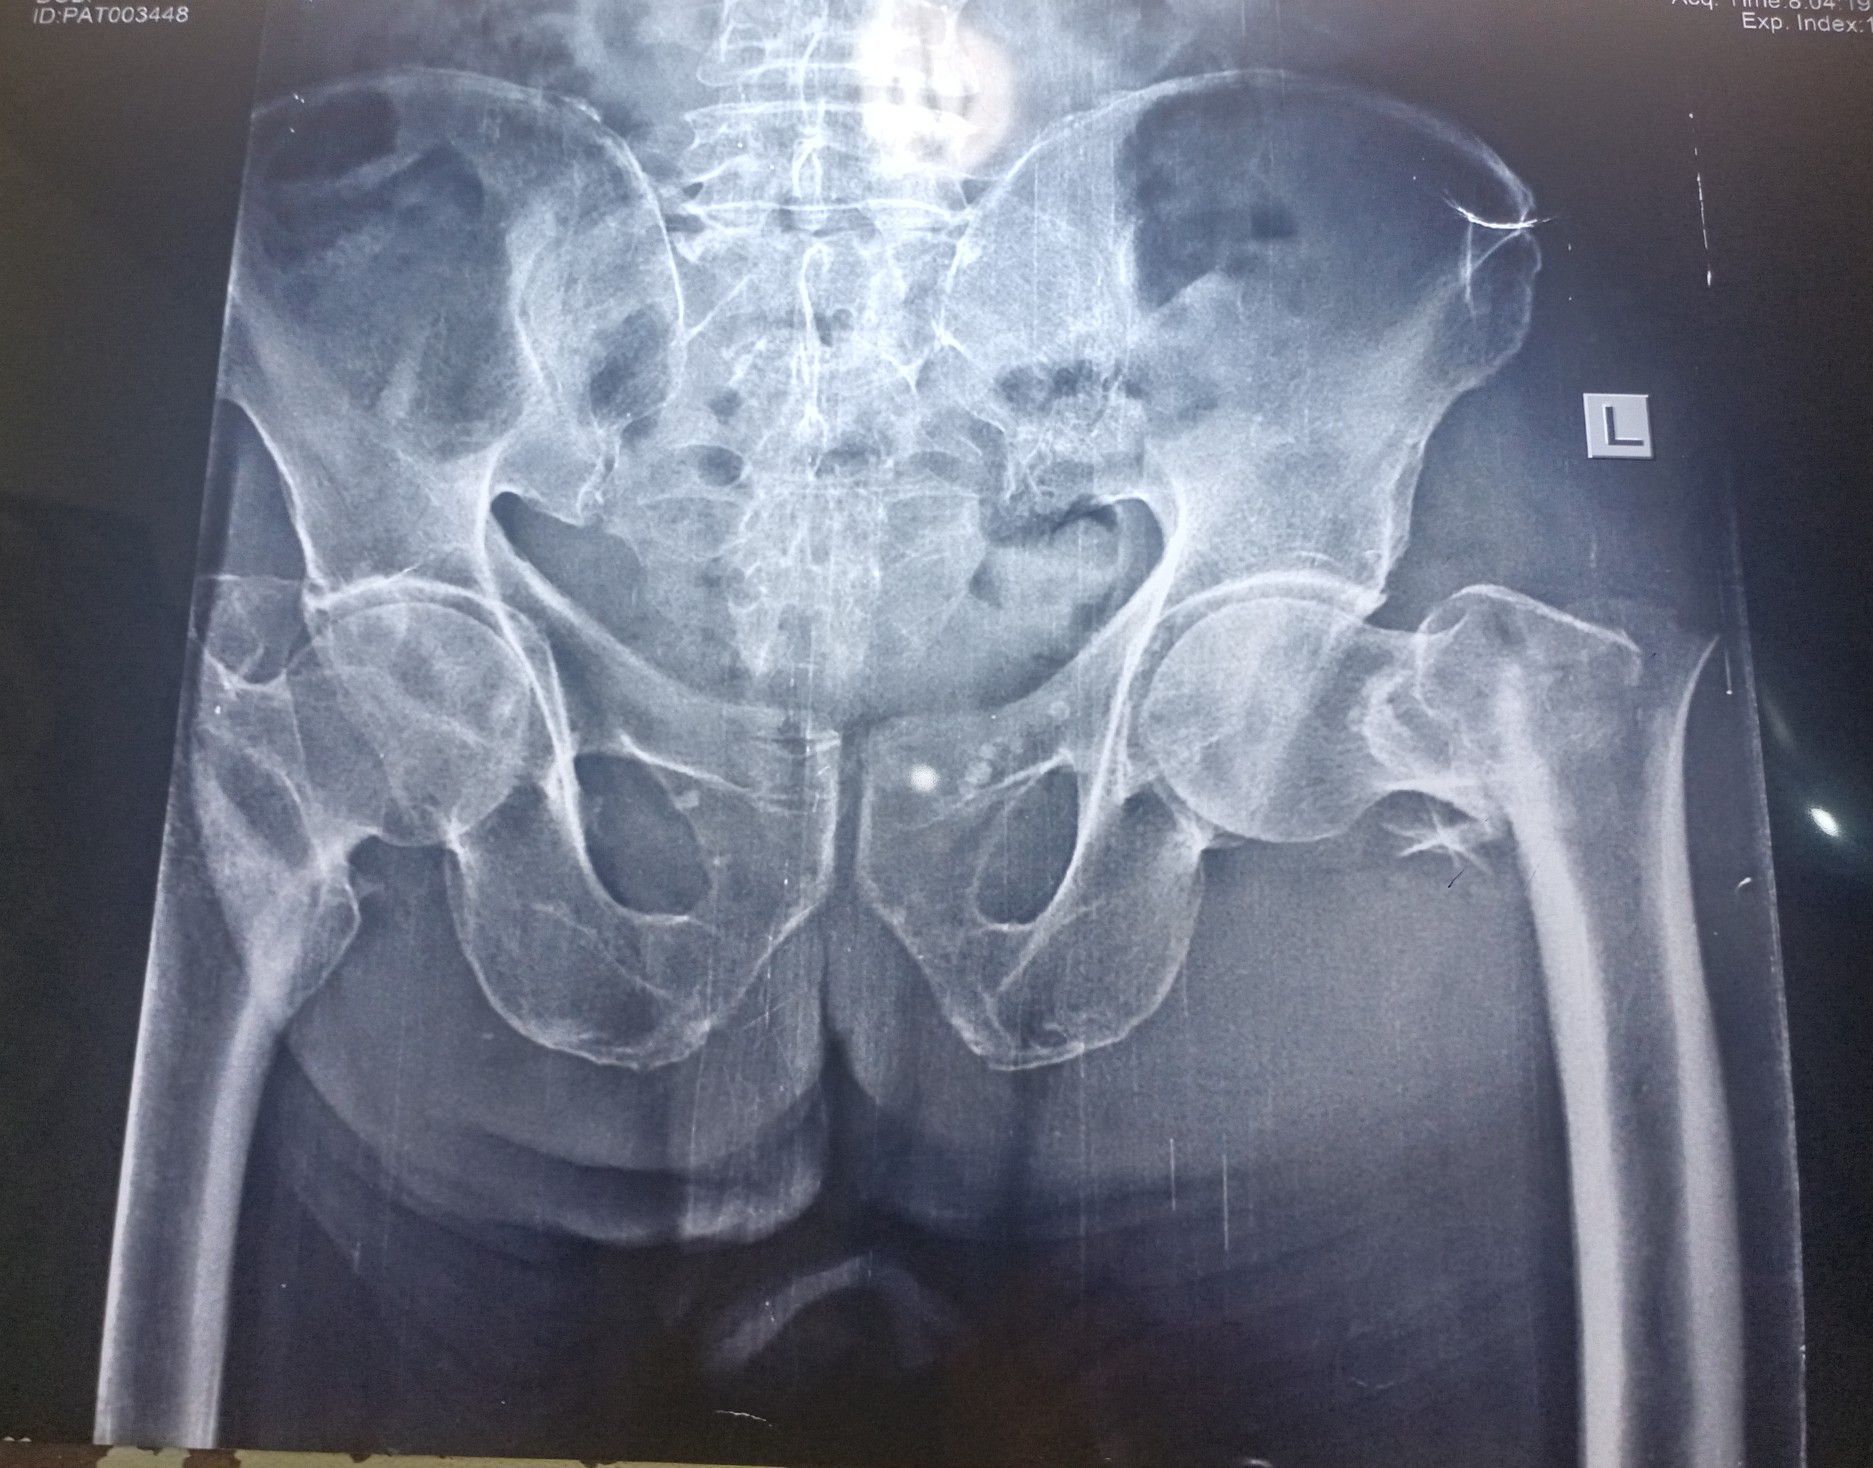

Neck of femur fracture

Fracture of neck of femur is common in old age , requiring hemi arthroplasty or total hip replacement surgery . In adults dynamic hip screws are used to prevent avascular necrosis.